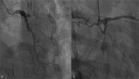

Interventions: Primary percutaneous coronary intervention (PPCI) was performed to restore the coronary flow of left anterior descending. Meanwhile, combination of oral glucocorticoids and immunosuppressive agents was administered to halt disease progression of TA.